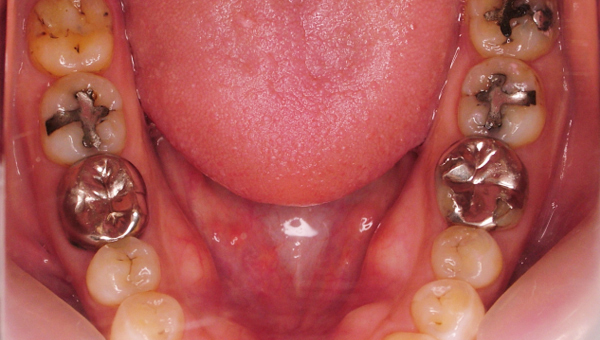

セラミックインレー前

セラミックインレー後

左右下顎6、7(4本) e-maxによるインレー治療

歯周病治療(歯石除去、歯みがき指導など)

治療期間 1か月

治療費 160,000円+消費税

副作用 局所麻酔によるアレルギー